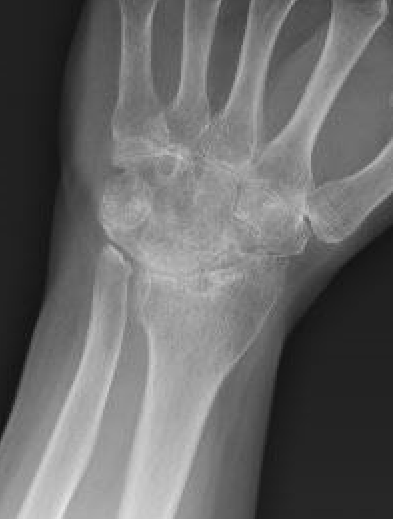

End stage rheumatoid wrist

Rheumatoid wrist